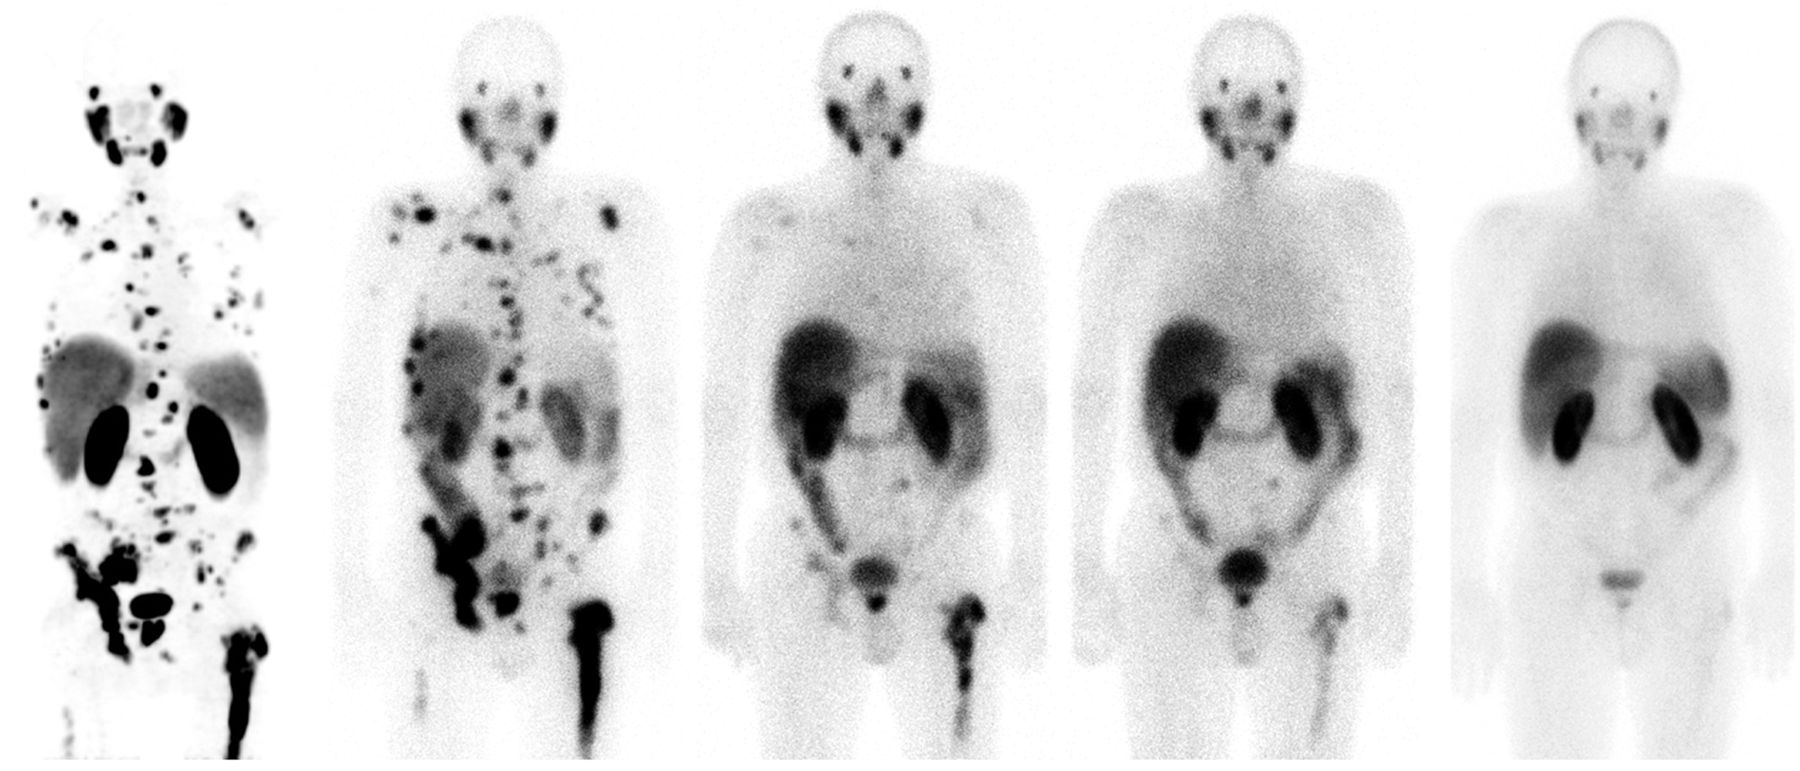

El médico José Luis Carreras se entusiasma cuando habla de la teragnosis, una pujante estrategia que funciona como un misil de precisión contra las células de algunos tipos de cáncer. Carreras, jefe de Medicina Nuclear en el Hospital Clínico San Carlos, en Madrid, habla de “resultados espectaculares” en determinados pacientes terminales. El médico recuerda el caso de un hombre alemán de 62 años, con cáncer de próstata y una diseminación masiva con metástasis en los huesos. Tras un tratamiento experimental con teragnosis en la Clínica Central de Bad Berka (Alemania), ocho meses después parecía limpio. Volvió a trabajar y a hacer deporte. Y tres años y medio después seguía libre de cáncer, según explicó Carreras en febrero en una sesión científica en la Real Academia Nacional de Medicina, en Madrid.

El médico Michael Morris, del Centro Oncológico Memorial Sloan Kettering, en Nueva York, ha presentado en el congreso de ASCO los últimos resultados de la teragnosis contra el cáncer de próstata avanzado. La técnica consiste en utilizar una molécula con alta afinidad por la PSMA, que es una proteína que suele estar en grandes cantidades en las células del cáncer de próstata. Para hacer el diagnóstico, esa molécula afín al PSMA se une a un elemento químico radiactivo, el galio-68, que brilla en una exploración con tomografía por emisión de positrones (PET). Para el tratamiento, la misma molécula se une a otro elemento químico, el lutecio-177, que emite una radiación local que mata a las células cancerosas. Es como disparar primero una flecha con una bombilla y después otra flecha con una pequeña carga explosiva.

En el ensayo de Morris participaron 831 pacientes con cáncer de próstata resistente a la castración y metástasis, un tipo de tumor habitualmente letal. Los enfermos que recibieron el tratamiento con teragnosis vivieron 15,3 meses, frente a los 11,3 meses de los hombres a los que se administró una terapia estándar. Cuatro meses de diferencia —un 35% más— pueden parecer poca cosa, pero se trataba de pacientes prácticamente desahuciados, en los que ya habían fallado la quimioterapia y los tratamientos hormonales.

El prometedor tratamiento experimental presentado en el congreso de ASCO, bautizado 177Lu-PSMA-617, estaba en desarrollo en la empresa biofarmacéutica estadounidense Endocyte. El gigante farmacéutico suizo Novartis anunció en octubre de 2018 la compra de esta compañía por unos 1.700 millones de euros. Algunas investigaciones previas, como un estudio con 30 pacientes en 2016 en el Hospital Universitario de Heidelberg (Alemania), ya habían mostrado el potencial de esta estrategia.